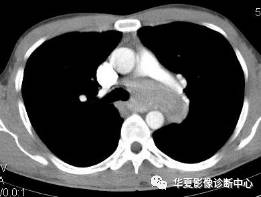

男性,32岁。无明显原因胸闷不适3月,胸片示纵隔及左肺门占位。

【CT征象】纵隔主肺动脉窗内见团状软组织肿块,最大截面约5.0cmX4.0cm,密度均匀,动脉期呈中度强化,延迟扫描呈明显强化,接近同期血管密度;左肺动脉干及左主支气管略受压。

【CT诊断】 ①巨淋巴结增生症;②淋巴瘤;③结节病;④淋巴结结核。

【最后诊断】纵隔巨淋巴结增生症。